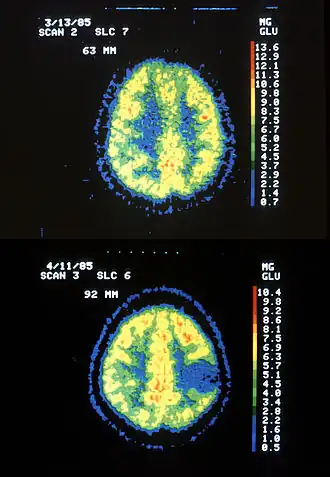

boven gezonde hersenen, onder met astrocytomen